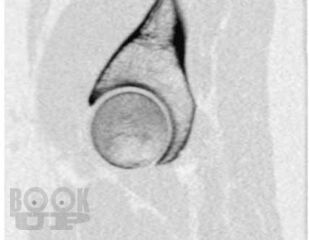

В основу книги положен многолетний опыт ультразвуковых исследований тазобедренного сустава в многопрофильной клинике с развитыми ревматологической и ортопедической службами. Проанализирован опыт отечественных и зарубежных авторов, суммированы результаты многочисленных оригинальных собственных исследований. Подробно освещены вопросы топографической и ультразвуковой анатомии тазобедренного сустава, технические особенности проведения исследования в том числе с использованием контрастных препаратов, проведения внутрисуставных инъекций под контролем ультразвукового исследования. Подробно описаны особенности ультразвуковой визуализации неизмененного тазобедренного сустава, широкого спектра патологических состояний и заболеваний дегенеративно-дистрофического, травматического, воспалительного генеза при использовании новейших и инновационных технологий эхографии. Дано подробное описание ультразвуковой картины при различных состояниях сустава: от асептического некроза головки бедренной кости, артрита, трохантерита, бурситов до бедренно-ацетабулярного импинджмента, ARS- и хамстринг-синдромов. В монографии представлены рациональные варианты и алгоритм диагностического поиска при патологии тазобедренного сустава с применением методов лучевой визуализации, определено оптимальное место ультразвукового исследования, даны подробные варианты описательной и заключительной частей ультразвуковых протоколов.